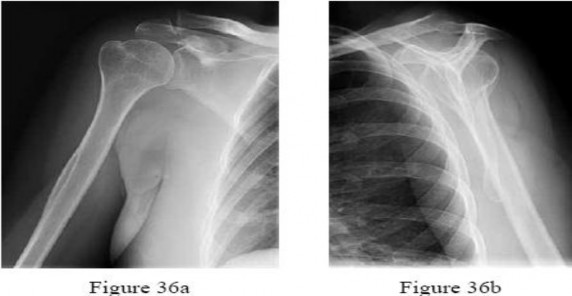

Question 10:

A 55-year-old carpenter presents with right shoulder pain and weakness after attempting to lift a heavy tool box. On physical examination, he demonstrates a positive drop-arm test and profound weakness with active abduction in the scapular plane. An MRI confirms a massive, retracted tear of the supraspinatus and infraspinatus tendons. Fatty infiltration of these muscles is graded. Which classification system is most commonly used to grade fatty infiltration of the rotator cuff muscles on imaging?

Correct Answer: Goutallier classification

Explanation:

The Goutallier classification is used to quantify the amount of fatty infiltration of the rotator cuff muscles, originally described on CT but now widely adapted for MRI. High grades of fatty infiltration (Goutallier 3 and 4) are associated with poor functional outcomes and higher re-tear rates following surgical repair.